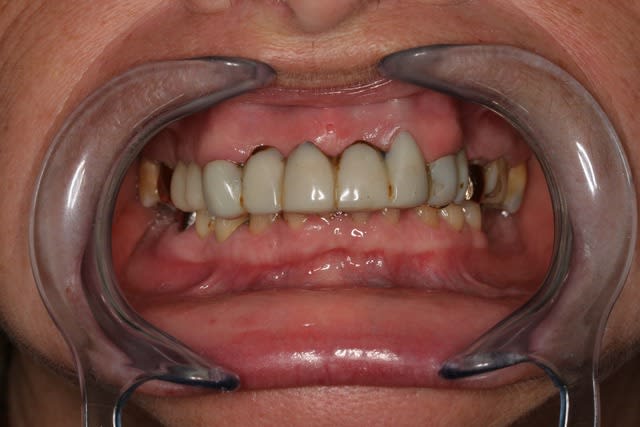

Et si y a pas d'ortho ça donne ça: Photos.

Cl2 fin1 nmz4p5 - Eugenol

Cl2 fin2 osbsl9 - Eugenol

Cl2 fin3 zucmck - Eugenol

Cl2 fin4 nr5a2i - Eugenol

Cl2 fin5 qsfof9 - Eugenol

La DV a été surélevé de plus de 2 mm et validé sur prés de 6 mois, et ça a été très difficile à obtenir, occlusion validé au Tscan, patiente hyperactive, je me suis arrêté de monter quand elle a commencée de râler, c'est un cas de compromis.